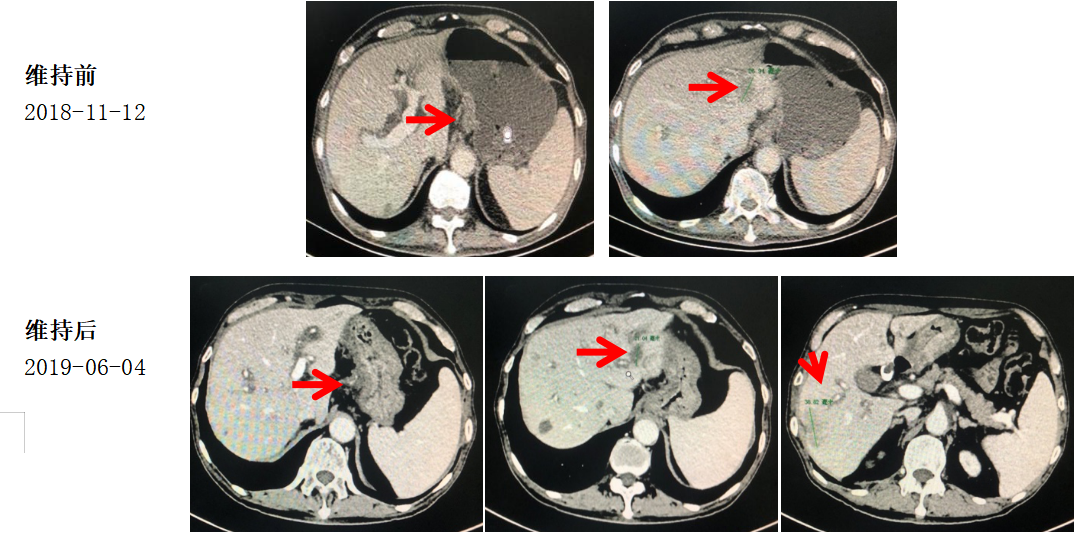

治疗经过:维持治疗

具体治疗方案:

替吉奥 50mg bid D1-14每3周重复

2018-12-12至2019-06-04,肝多发转移灶,部分结节较前增大,CA199进行性(147.90U/ml-1275U/ml)升高,8周期替吉奥单药维持治疗后肿瘤PD。建议明确HER2状态,转二线治疗。